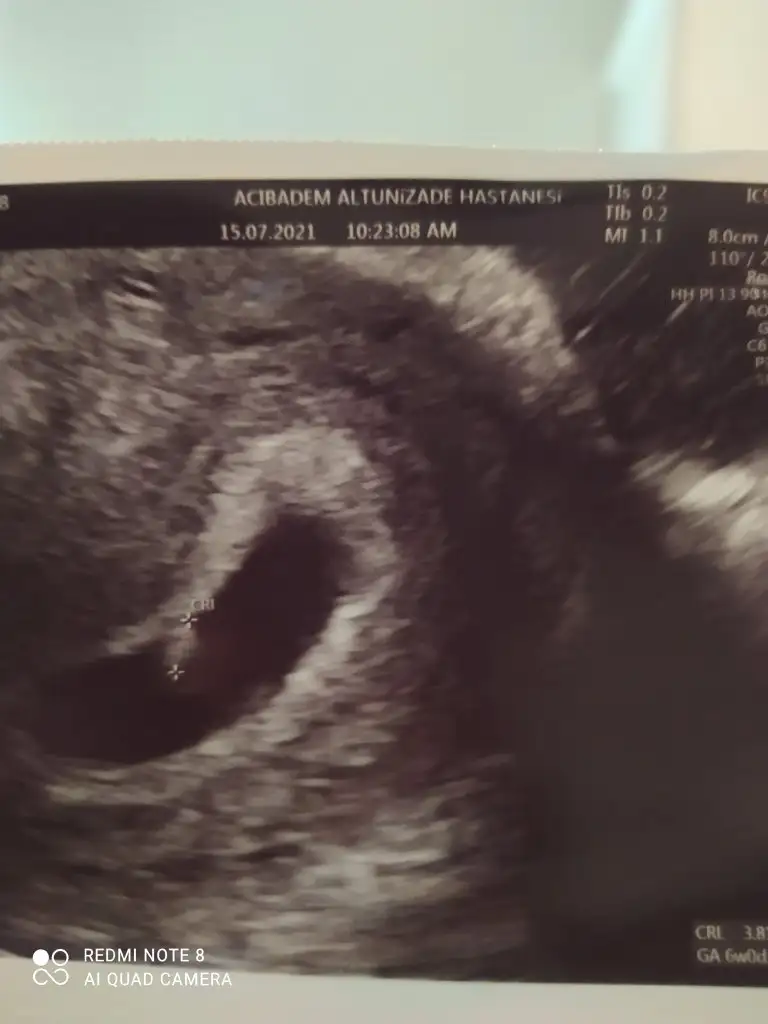

Maşallah size inşallah böyle devam ederselamlar herkese :) biz de dün bebeği ve kalp atışlarını gördük çok şükür. geride 2 yaş bebesi olunca uyku hali gibi lüksüm olmuyor maalesefkızımda da bulantım olmamıştı bunda da yok şimdilik. kendimi iyi hissediyorum tüm gün hareket halindeyim diyebilirim. herhangi bi ağrı sızı kanama lekelenme gibi şikayetlerim yok bizden de haberler böyle :)